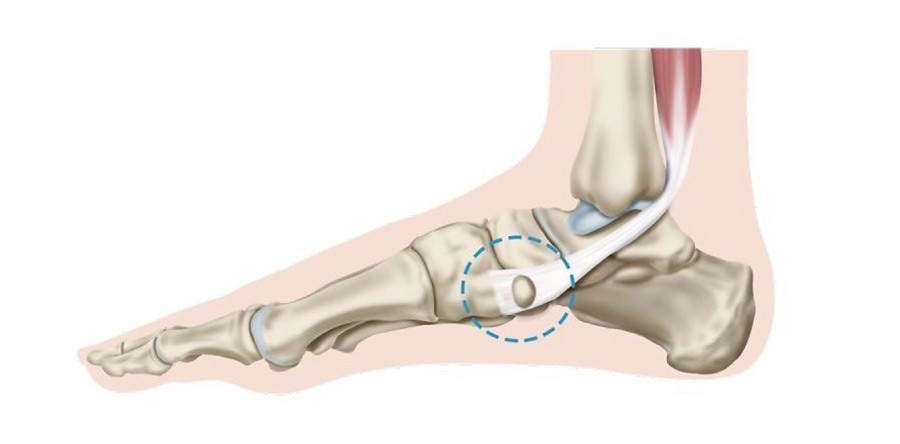

초기에는 밤에만 불편함을 느끼다가 점점 지속 시간도 늘어납니다.3. 족저근막염

발바닥 통증의 대표 질환으로,

발뒤꿈치에서 발바닥 전체로 이어지는 근막에 염증이 생기며

걷거나 서 있을 때 발바닥이 뜨겁고 찌릿한 통증을 유발합니다.

특히 아침에 첫 발을 디딜 때 더 아픈 경우가 많아요.